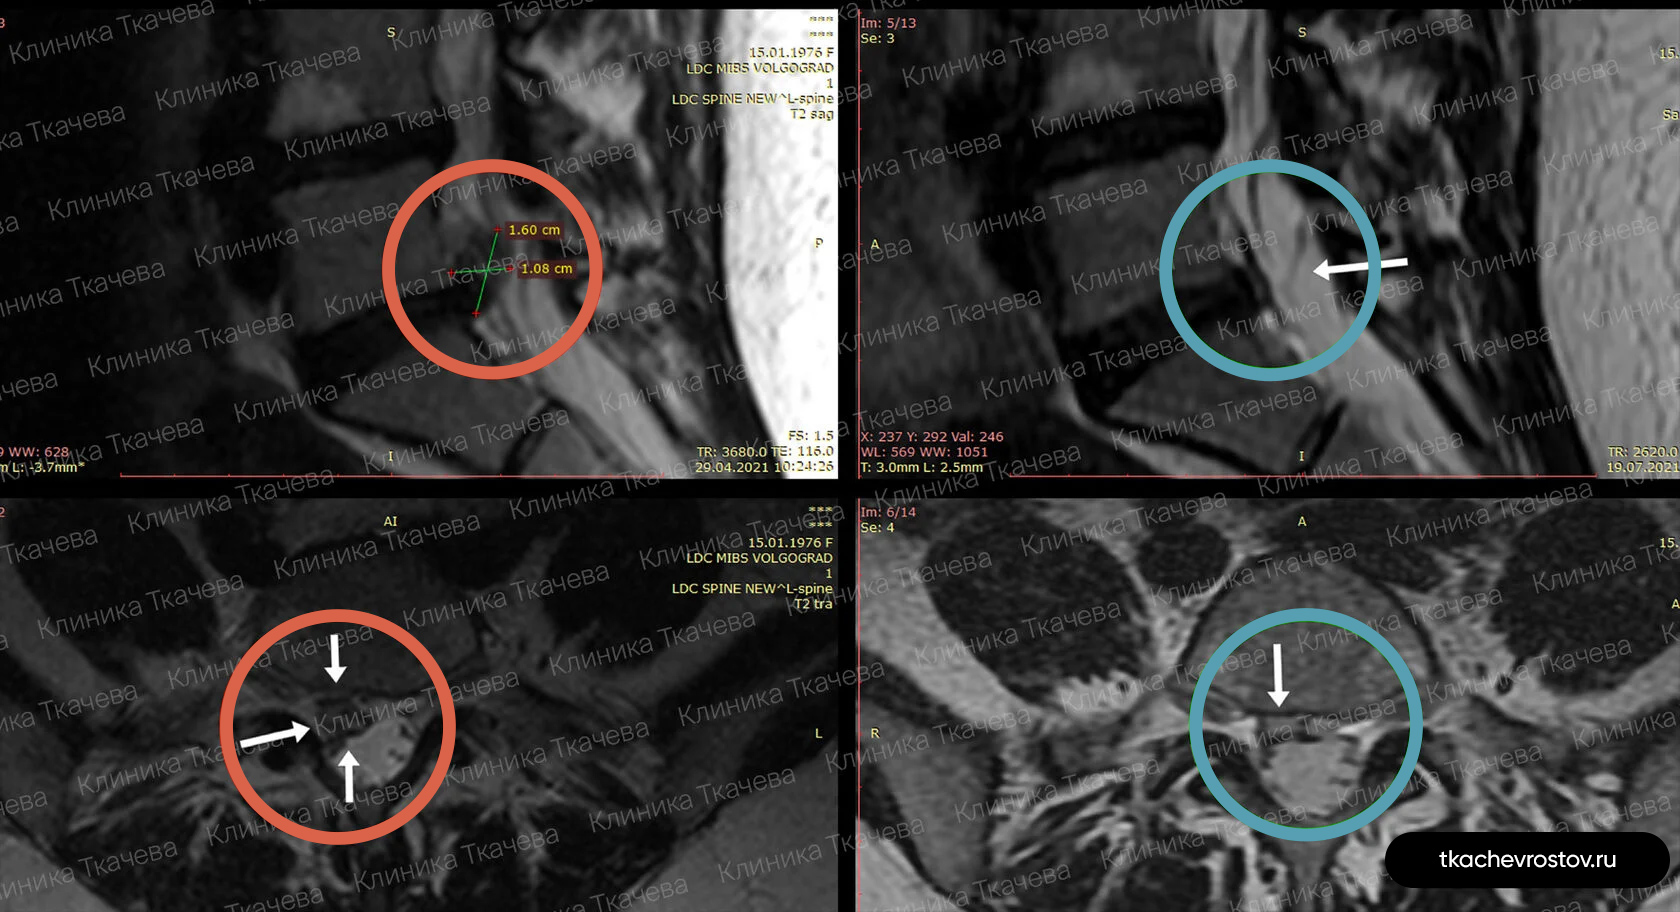

Грыжа в шейном отделе C6-C7

Женщина. Грыжа в шейном отделе C6-C7 1.8х0.8см. Из-за боли передвигалась по стеночке. Отказалась от операции по квоте – замена диска на имплант.

ДО:

- Больно дышать и говорить

- Какие-либо движения головы приносили жуткую боль

- Правая рука не слушалась, частично онемели ладонь и пальцы руки

- Обезболивающие, блокады, капельницы. Ничего не помогло

- Потеря трудоспособности и ограничение жизнедеятельности

ПОСЛЕ 1 курса:

✓ Наступила резорбция грыжи

✓ Наступило улучшения общего состояния

✓ Стала лучше работать правая рука

✓ Ушло частичное онемение

✓ Голова стала поворачиваться во все стороны

✓ Ушла выраженная боль и напряжение в шее

✓ Пациентка смогла сесть за руль

ПОСЛЕ 2 курса:

✓ Полная резорбция грыжи

✓ Восстановление всех двигательных функций

✓ Прекрасное самочувствие

Всё лечение заняло полгода (2 курса по 15 дней).